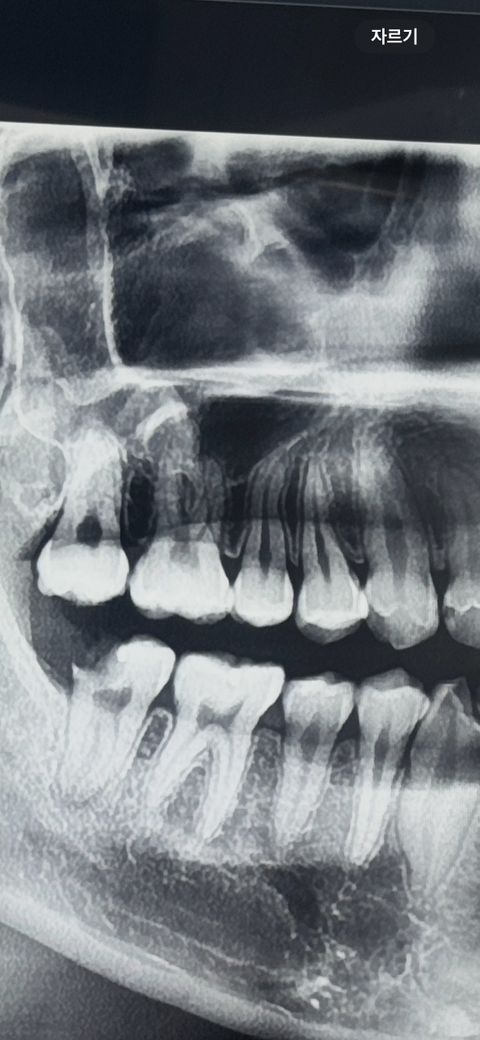

상악동 안에 치아가 있는것이 맞나요?

엑스레이상 상악동안에 치아가 있다고 들어서요

상악동에 방사선 불투과상이 보이긴 하지만 치아인지는 확실하진 않습니다. CT촬영을 해보셔야될것같습니다.

지금 이 파노라마 사진으로 보아서는 상악동 안에 치아는 없습니다. 어금니 뿌리가 상악동과 겹쳐 보이는 정도입니다.

사진으로 봤을 경우에는 상악동 안에 치아가 있을 수도 있지만 상악동이 아닌 치족을 내부에도 있을 수 있습니다. 사진은 3차원 사진이 아니라 2차원 사진으로 보이기 때문입니다

보험 되는지도 알려주세요.. -> ct 찍어봐야 할것 같습니다 보험은 적용됩니다